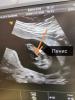

Кто узнавал пол на сроке 16-17 недель , можете покидать фотки с узи)) мне с сыном в 16 недель сказали и там уже было не спутать 😄

Вот реально, пацанов не перепутаешь 😂😍

Результат был 100%,я сказала если 98% то не писать пол

@lovemimisha, я ходила в клинику ,они там ещё через 3д смотрят ,так что прям 100%